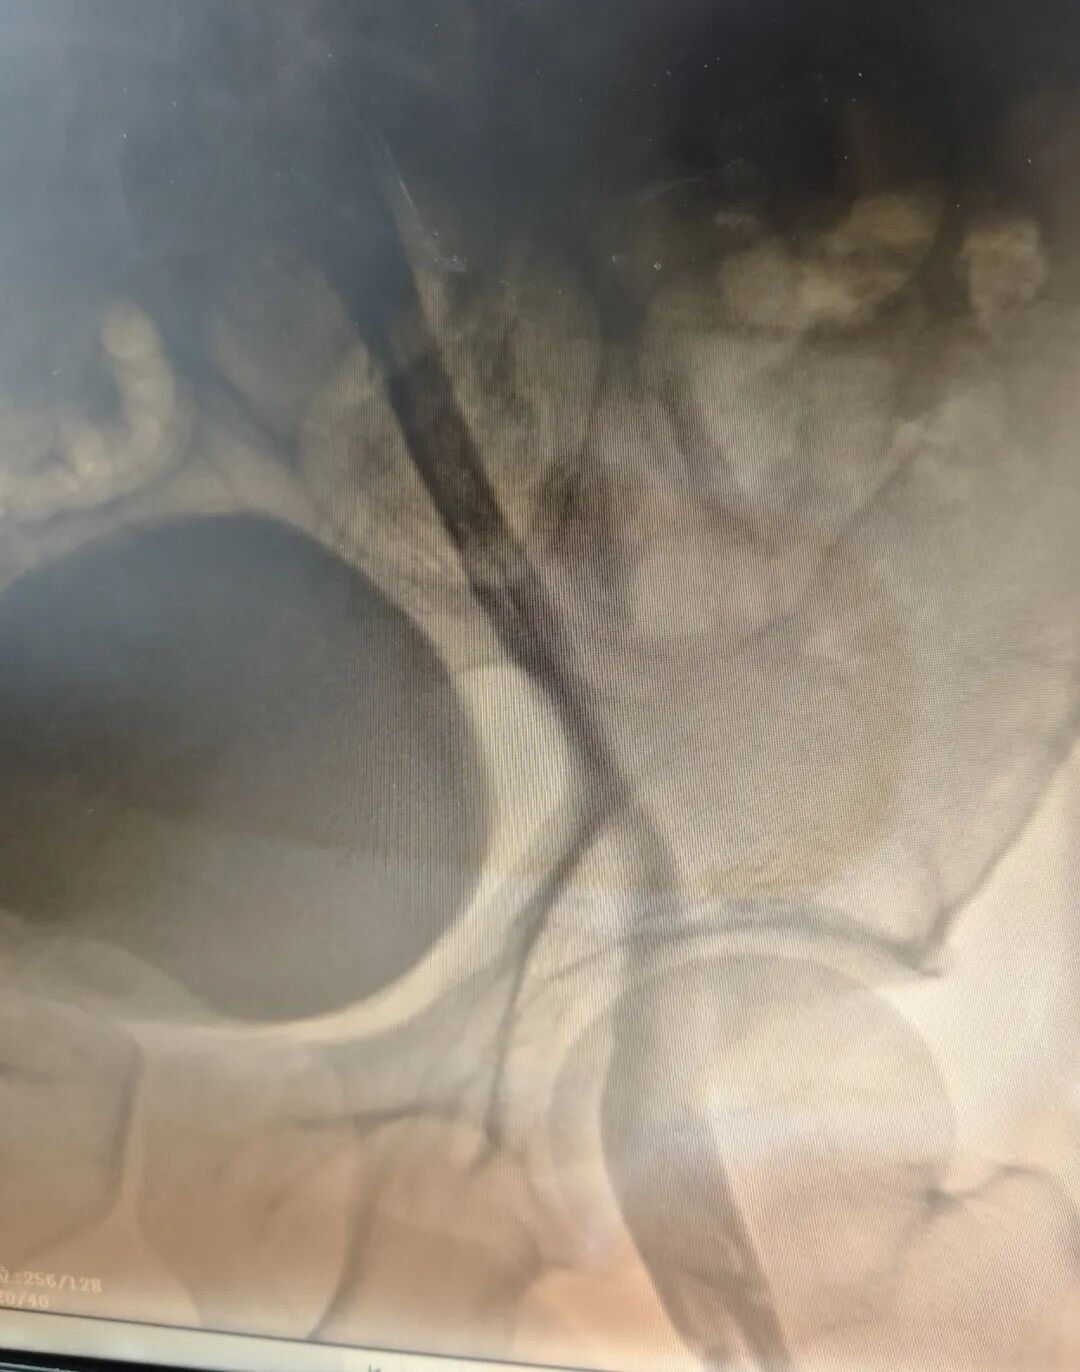

田明主任精准操作,经鞘管将静脉取栓支架推送至髂总静脉,并一路延伸至股浅静脉,通过四次小心翼翼的反复拉栓,成功清除大量血栓。最终,复查造影传来捷报:患者股浅静脉、髂静脉及股静脉血流通畅,未见残余血栓,手术获得圆满成功!这一结果让手术室里的所有人都松了一口气,也意味着这场与病魔的激烈较量取得了阶段性的胜利。

术后造影